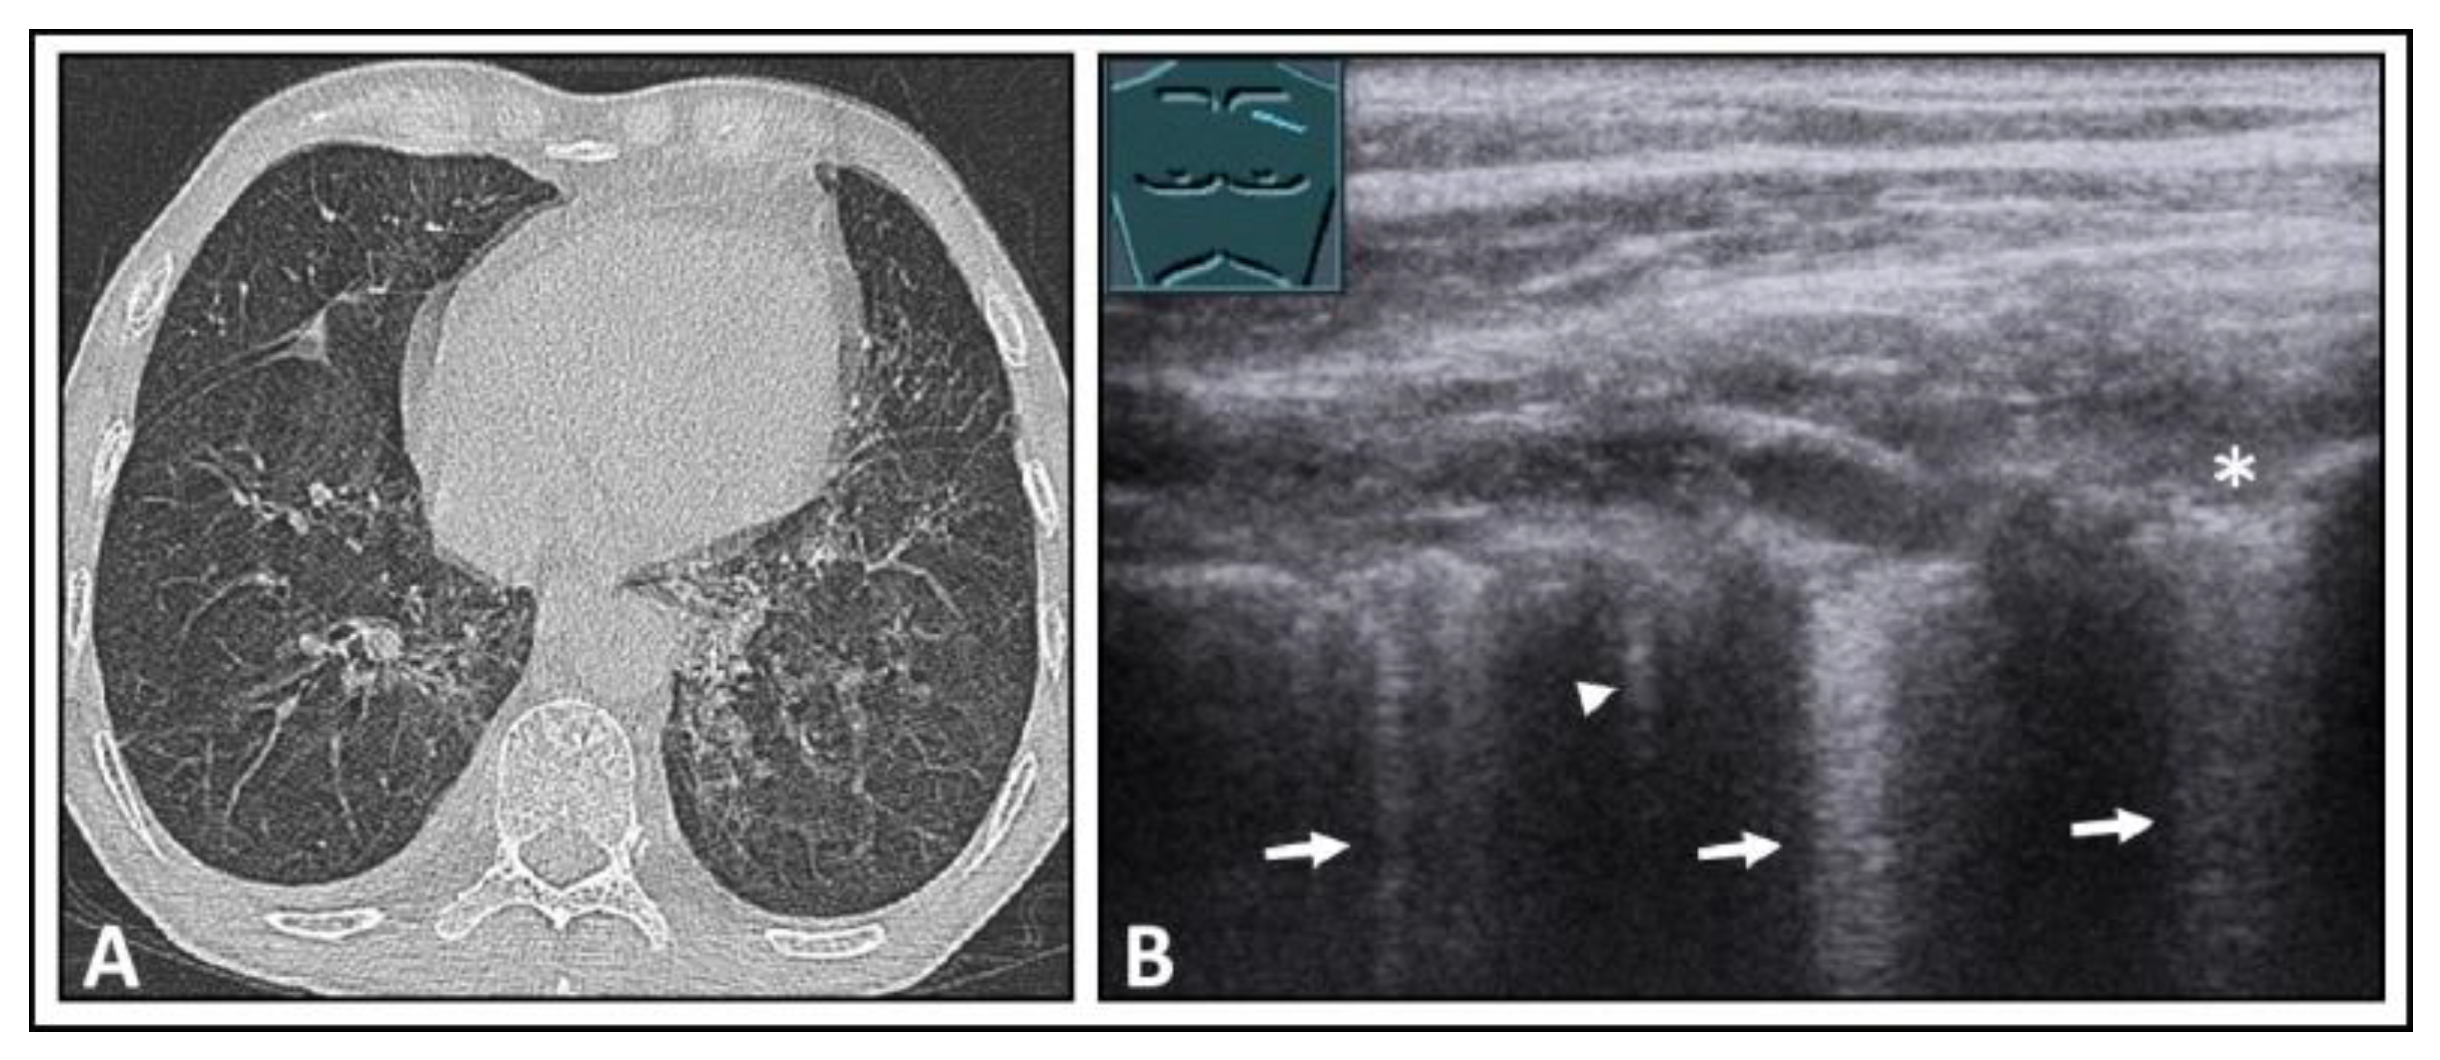

7. Other Pathologic Situations